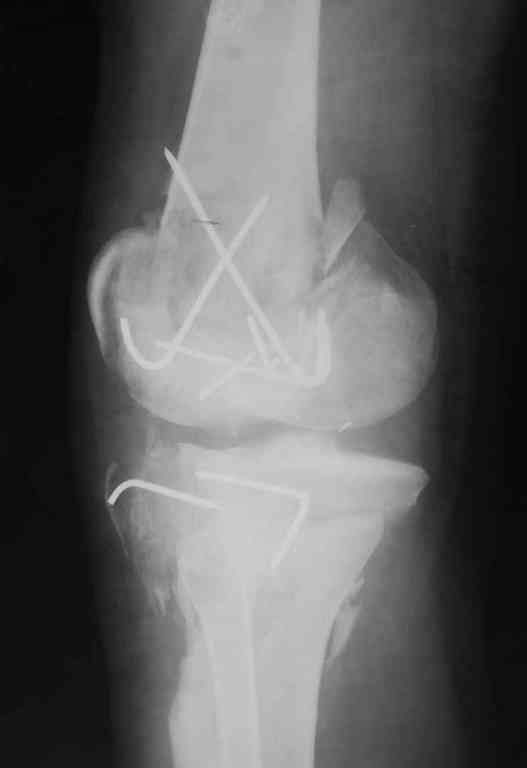

Re: Последствия открытого перелома дистального отдела бедра

Коллеги фиксатор Numelock II